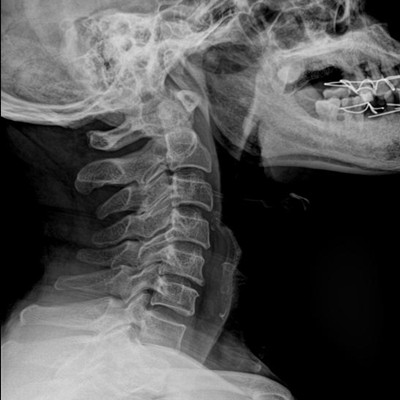

●探測(cè)器可以大范圍轉(zhuǎn)動(dòng),大尺寸有效探測(cè)面積,可滿足人體多部位攝影需求。